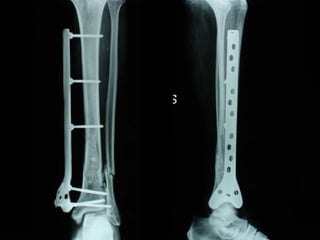

Dal Gennaio 2000 al Febbraio 2006 abbiamo trattato 167 fratture chiuse  con placca percutanea  in 164 pazienti :  27 lesioni diafisarie di gamba, 12 piloni tibiali ,  11 fratture prossimali di tibia, 36 fratture sovracondiloidee di femore, 17 fratture diafisarie di femore, 43 fratture metaepifisarie prossimali di omero, 21 diafisarie d’omero.  156 guarigioni 8 fallimenti

I buoni risultati ottenuti dipendono da 5 punti fondamentali:   una accurata riduzione percutanea della frattura  precise vie di accesso  l’utilizzo della placca che consenta il più lungo braccio di leva possibile il pretensionamento della placca  una sintesi con un ridotto numero di viti

Placche lunghe e pretensionate

Placche lunghe e pretensionate Sintesi con un ridotto numero di viti

VANTAGGI CHIRURGIA MININVASIVA Mini Open Inserimento della placca sottocutaneo per scivolamento Viti percutanee Preservazione dei tessuti molli Ridotto danno vascolare Rapida ripresa funzionale

Conclusioni Riduzione  anatomica Minimo trauma chirurgico Corretto equilibrio fra elasticità e stabilità Precoce mobilizzazione